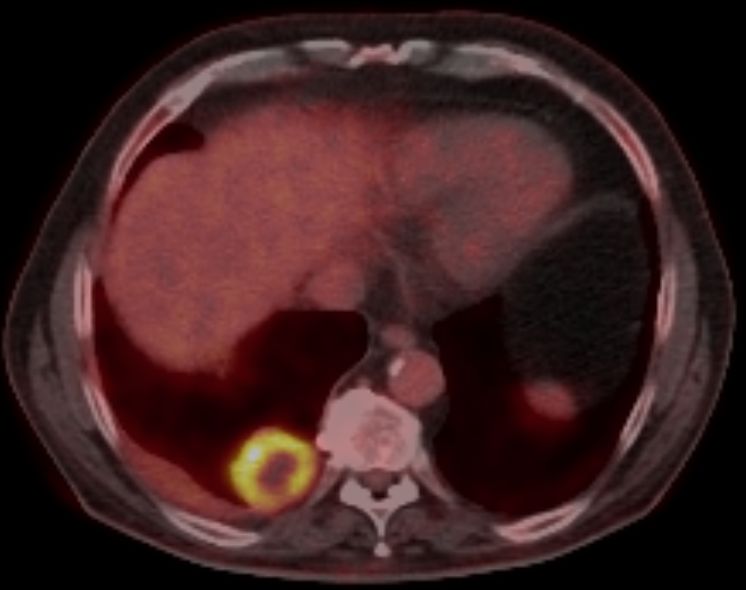

| Schwanom des Thorax | 79-jähriger Mann mit einer unklaren Raumforderung im rechten Unterlappen. Thorakoskopisch großer nekrotisch zerfallender Tumor. Pleurale Raumforderung i.S. einer Abklatschmetastase. Histologisch spindelzellige Proliferate, vergrößerte hyperchromatische atypisch geformte Zellkerne. Z.T. mehrkernige Riesenzellen. Im Zentrum ausgedehnter nekrotischer Zerfall. Histochemie: CD34, Panzytokeratin, EMA, Alfa-Aktin, Caldesmon, HMB45, Melan A und Zytokeratin A negativ. Vimentin überwiegend positiv | ||

Das PET-CT zeigt massiven Stoffwechsel in der Randzone des Tumors.![]() |